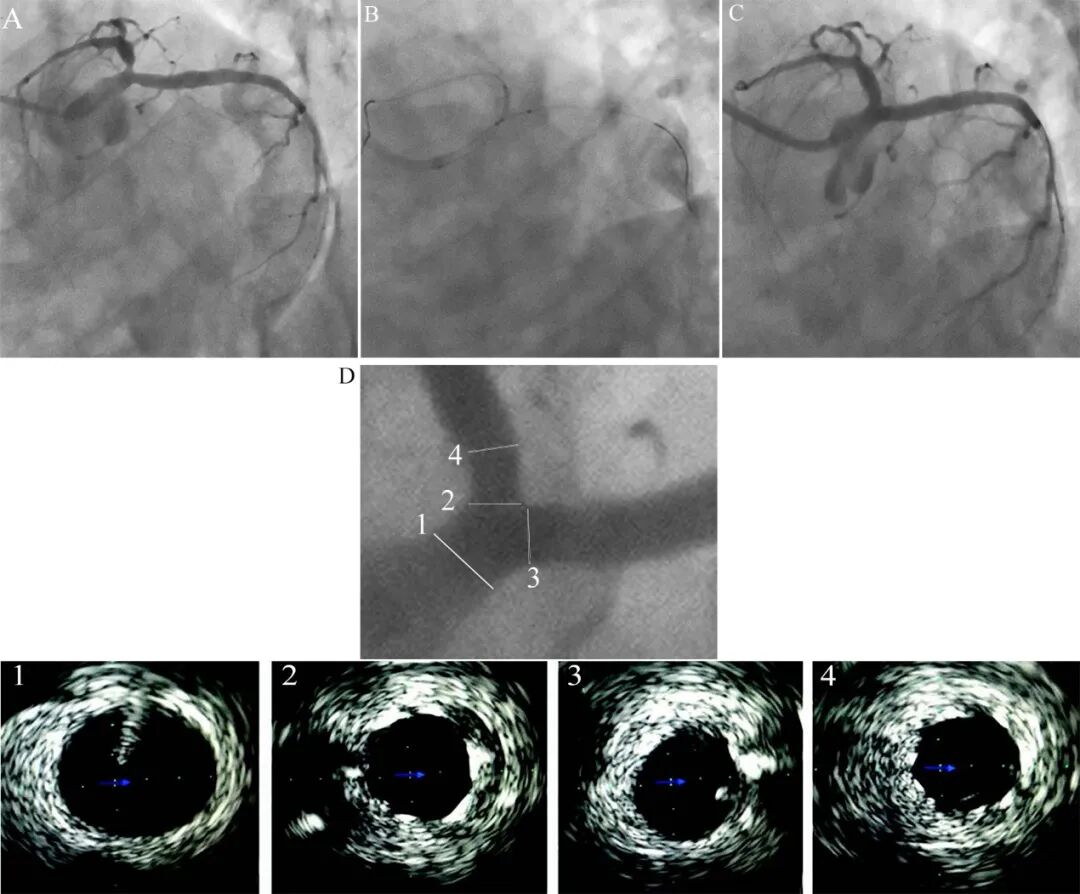

图4 花瓣技术案例[3]。

A 前降支开口病变(蜘蛛位),B花瓣技术支架定位,C 最后造影结果。D IVUS证实支架定位良好,完全覆盖前降支开口,没有发生斑块移位或血管脊移位。